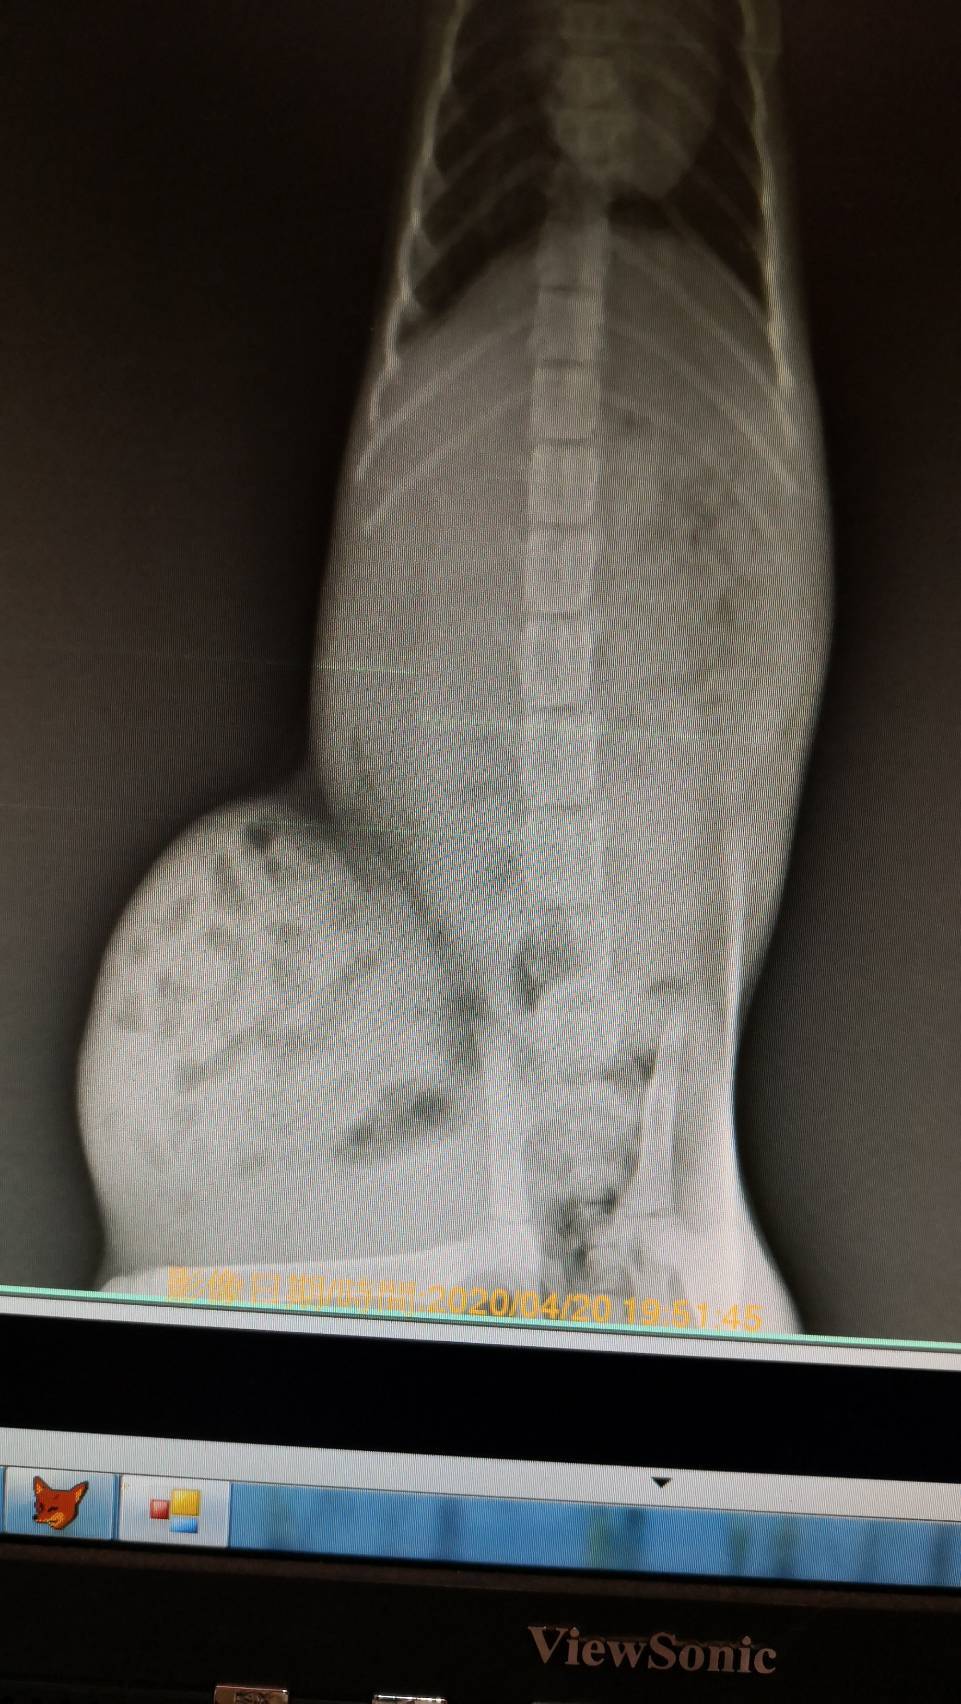

主題: 被車撞到的小貓平安 申請者姓名: 梁仕宏 花色: 申請日期: 2020-05-15 15:12:04 申請者部落格: 申請者臉書網址: 梁仕宏 所在縣市/合作醫院: 高雄市/小新動物醫院 治療費用: 5000元 需求人數: 22人 已結案 (2024-05-31 18:16:25) 報名人員: philtery x10(已付款)、艾曼達、艾曼達 x7、艾曼達 x4(已付款)、粉圓(已付款)、派派 x5(已付款)、superwu、superwu(已付款)、Candice(已付款)、 候補人員: 動物病情說明: 安安是隻約三個月大的小賓士,可能是年紀太小不會過馬路,又或是因騎士沒注意而撞到牠,牠被撞後緊張逃進路邊診所,好心的工作人員洽好是社團貓友因而在社團求援,由於案發地在我家附近,通報時間又是4月13日晚上近9點,時間非常緊迫,怕醫院近關門時間,所以我立刻到現場救援並聯絡醫院等我將牠送醫。 動物近況說明: 安安在醫院積極幫忙治療下,經過兩三天已脫離險境,身體狀況也好轉,但醫院再次觀察她,卻發現可能因為車禍關係產生赫尼亞現象,建議第一階段住院完成後休養2-3週再進行腹腔修補手術。在她住院期滿先行出院安置期間,她變的非常可愛親人,中途點也幫她洗澡整理,也積極幫她找家。非常值得慶幸的是,有好心的家庭願意認養,而且她的赫尼亞現象也持續改善,所以再帶她回醫院複診,確認修補手術可合併日後結紮一起進行。感謝協會,醫院,大家的幫忙,讓她度過被撞可能失去生命的難關,找到她未來的幸福。